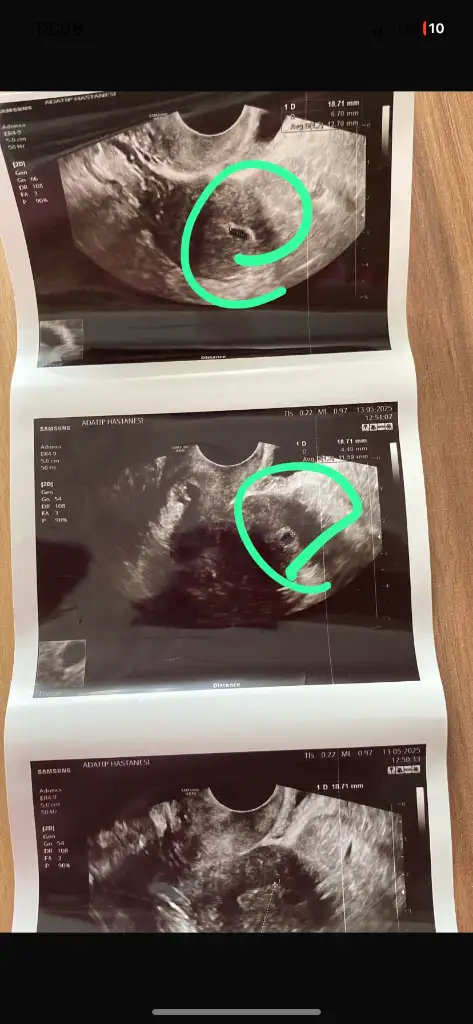

Bizim kesemiz 11mm olmuş sıra kalp atışında inşallah sorun çıkmaz korkuyorum açıkçası ama çok şükür daha net gözüktü kese

Bugün gittim evet kese var yine 11mm dedi cuma tekrar kontrole gitcem suan bir sıkıntı yok ama doktor kalp atışını duyana kadar risk her gebelikte vardır dedi